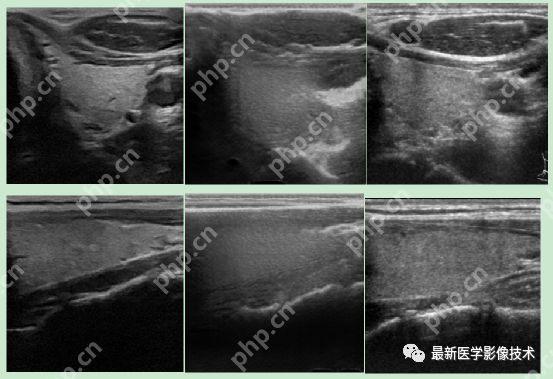

5、验证集部分生成结果

左图为低质量图像,中间为生成的高质量图像,右图为真实的高质量图像。